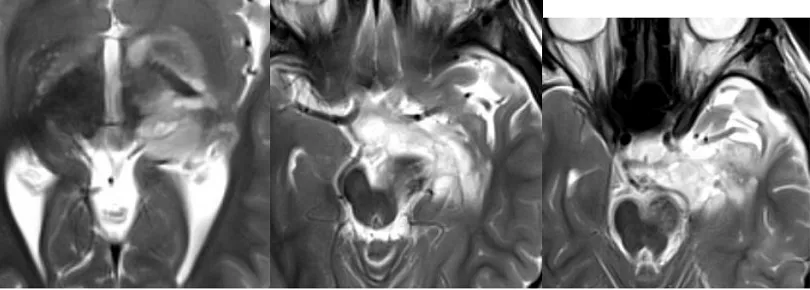

根据杨女士的回忆,当时问诊的神经外科医生仔细查看了患儿的影像资料,发现虽然存在多处占位性病变,未见弥散受限。结合临床病症,初步诊断是低级别肿瘤性病变,考虑是胚胎发育不良性神经上皮瘤或节细胞胶质瘤,建议立即手术。

但是可可只是切除了左侧颞叶和海马体附近的肿瘤,丘脑,基底节,大脑脚仍有残余。根据当时医生的说法,这些位置太深,手术很可能造成孩子瘫痪等,因此残留部分。然而手术后孩子出现了动眼神经麻痹、斜视、弱视,医生表示是一过性症状。确实经过经按摩和康复治疗后现已基本恢复正常,癫痫术后也未再发作。“该肿瘤属于良性肿瘤,如果手术可以全切,预后良好。虽然还有残余,但是比较少,可以先观察随访。”医生的话让杨女士悬了一个月的心终于可以放下了。

半年内该残留增加了2-3毫米,医院建议再次手术,但丘脑,基底节和大脑脚部分仍是手术风险大,无法切除。而且该说要把孩子的颞叶切了,杨女士慌了。没想到原本良性的肿瘤,现在却面临着2次开颅……